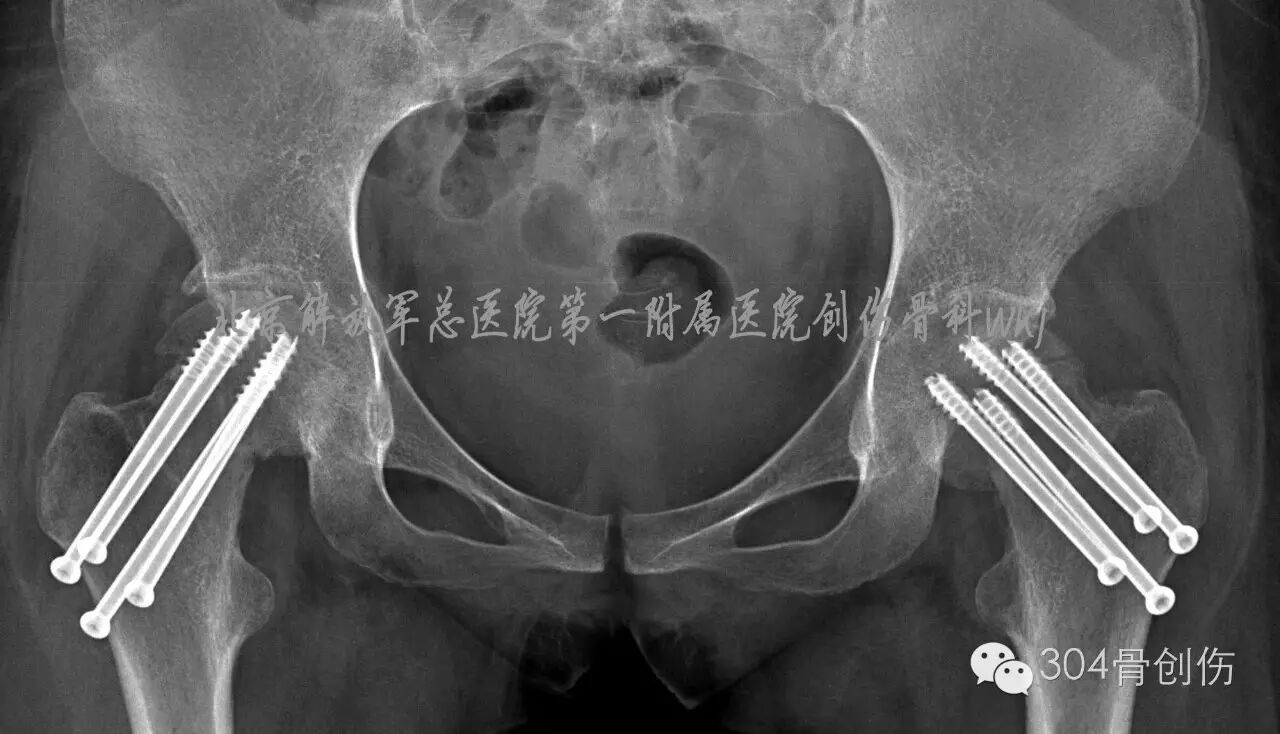

女,31岁,主因“双侧髋部疼痛活动受限6周”就诊。病史:患者孕36周时,扭伤跌倒,双髋部疼痛,活动受限,不能站立。X线显示:双侧股骨颈骨折,暂行保守治疗,待分娩后处理骨折。孕39周剖腹产一男婴,产后3周入304创伤骨科治疗。入院查体:体重50kg,身高156cm,双下肢外旋畸形,双大腿近端前外侧压痛,双下肢纵向叩击痛阳性,诊断:双侧股骨颈陈旧性骨折(Garden Ⅳ型-图)。

图-患者伤后X线片

(盆腔内为胎儿头颅)

全麻下双侧股骨颈骨折闭合复位内固定。在C型臂透视下,牵引床辅助闭合复位,固定股骨头、下肢极度内旋,骨折复位满意,为增加固定强度,双侧各经皮打入4枚空心螺钉(图)。术后口服钙尔奇600mg每天2次,骨化三醇胶丸0.25ug 每天3次。双腿非负重活动。